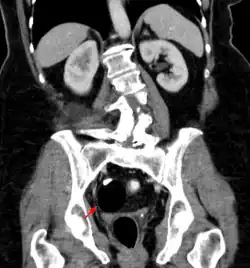

CT showing a teratoma of the ovary: fatty formation with a smooth boundary, with a dense part, possibly a tooth.

Teratomas are thought to originate in utero, so can be considered congenital tumors. Many teratomas are not diagnosed until much later in childhood or in adulthood. Large tumors are more likely to be diagnosed early on. Sacrococcygeal and cervical teratomas are often detected by prenatal ultrasound. Additional diagnostic methods may include prenatal magnetic resonance imaging. In rare circumstances, the tumor is so large that the fetus may be damaged or die. In the case of large sacrococcygeal teratomas, a significant portion of the fetus' blood flow is redirected toward the teratoma (a phenomenon called steal syndrome), causing heart failure, or hydrops, of the fetus. In certain cases, fetal surgery may be indicated.